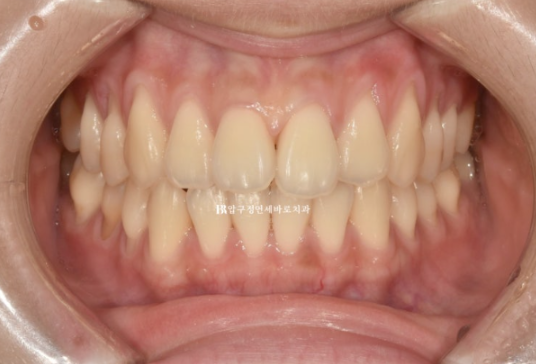

치료 전 - 치료 후 비교 사진입니다.

초진 24.02 이며 치료 종료는 24.07입니다.

24.02~24.07

소량의 치간삭제로 블랙트라이앵글 없이 치료를 마무리 했습니다.

좋은 교합은 유지가 되었고

토끼이빨은 정상 배열을 찾앗습니다.

깔끔해진 미소를 가지게 되었습니다.